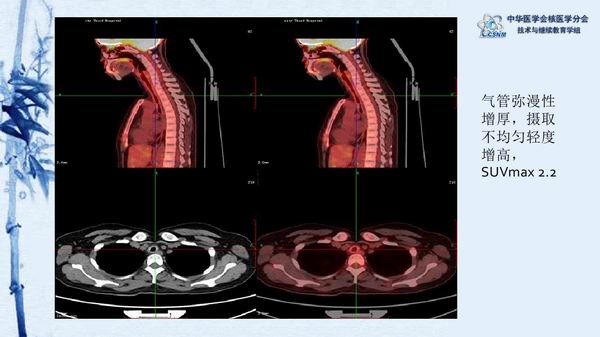

讲座15:复发性多软骨炎-张卫方